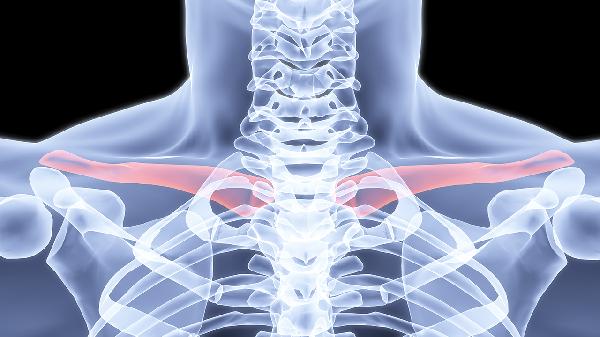

单纯线性骨折仅需简单固定,费用约2000-4000元;粉碎性骨折或伴有移位的骨折可能需多次手法复位,费用可达5000-8000元。儿童锁骨骨折愈合快,通常费用低于成人。